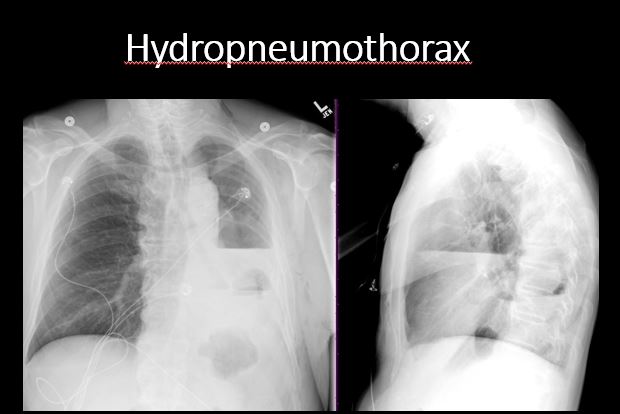

There is a pneumothorax, hydro/pneumothorax, or hemo/pneumothorax. [Yes/No]